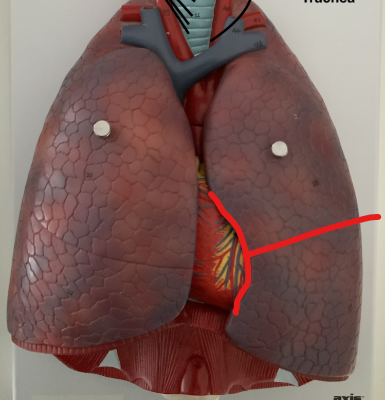

What structure is this?

Horizontal fissure of right lung

What structure is this?

Oblique fissure of right lung

What structure is this?

Oblique fissure of left lung